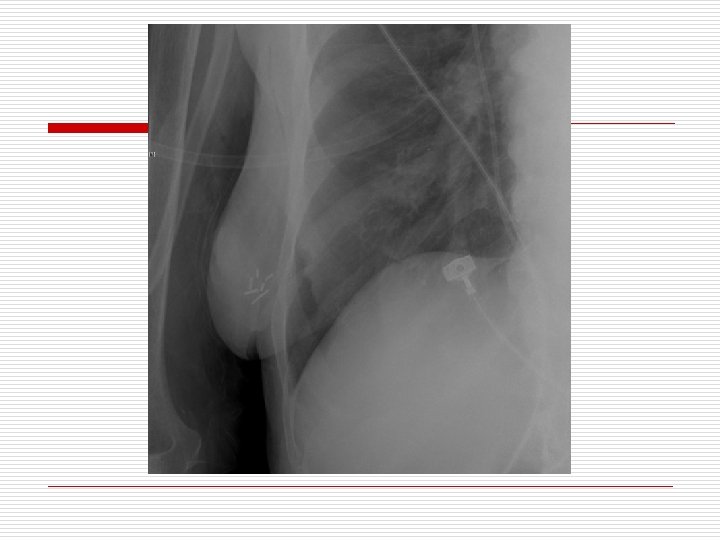

A 77 year old woman is brought to the ER for respiratory distress and emergently intubated. The ICU team is called due to hypoxia, tachycardia, and elevated airway pressures. Physical exam reveals harsh sounds on the right side with greatly decreased sounds on the left side.

A. B. C. D. The most appropriate treatment is: Needle decompression of the right side Needle decompression of the left side STAT Albuterol treatment Urgent CXR